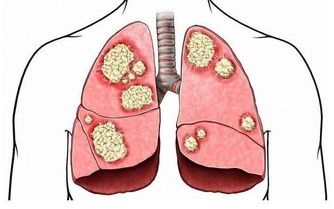

秋天容易感冒。如果肺部虛弱,就不足以抵禦外界的空氣,肌肉表面不結實,容易出汗,易受外界有害氣體的侵襲而常感冒,而外界有害氣體侵入肌肉表面,並常引起肺部疾病。皮膚由肺部支配。